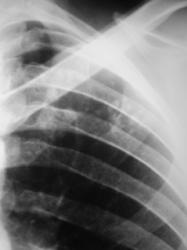

Гражданин С., 35 лет, жалоб не предъявляет. После прохождения профилактической флюорографии (иллюстрации 1, 2) «взят на контроль».

Определяется некоторое усиление и обогащение легочного рисунка в медио-базальных отделах с обеих сторон. Слева под ключицей, на фоне 1 межреберья и 2 ребра определяются очаги средней и малой интенсивности. На фрагменте флюорограммы (с увеличением изображения) не исключается «кавернизация очагов».